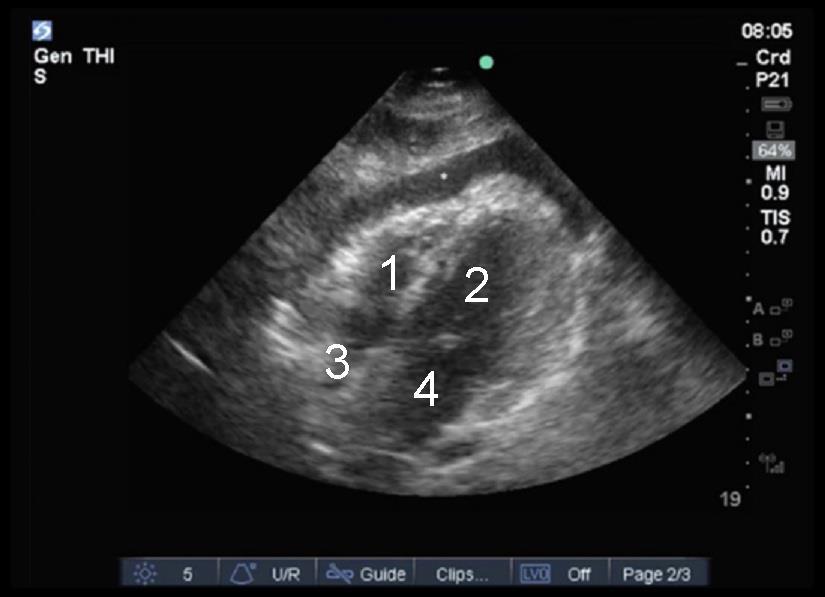

Heart Subxiphoid Moderate Effusion Image

1. Right Ventricle (RV)

2. Left Ventricle (LV)

3. Right Atrium (RA)

4. Left Atrium (LA)